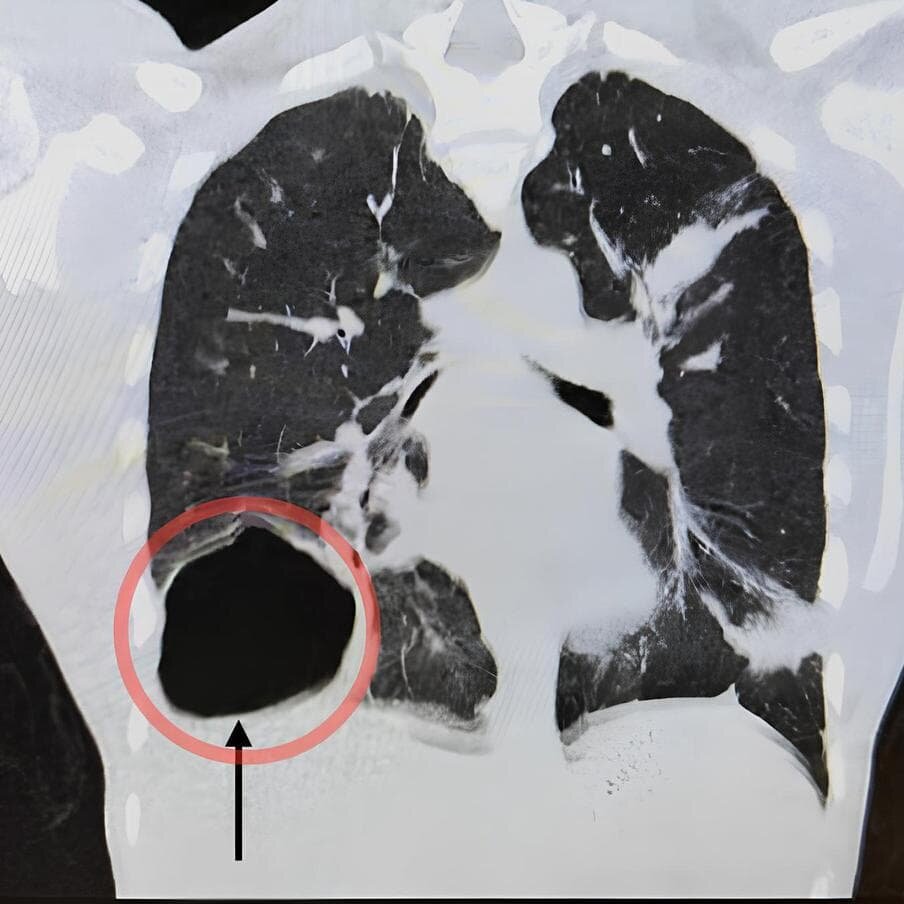

Вот так выглядела киста на рентгеновском снимке.пресс-служба МОЦОМД

17-летний молодой человек обратился в больницу с жалобами на кашель, слабость и боль в груди. Казалось бы, классические симптомы пневмонии, но проведённые исследования выявили в правом лёгком большую кисту с эхинококками – паразитами-гельминтами. Размер кисты составлял 7–8 сантиметров в диаметре, это всё равно что теннисный мяч в лёгком.

По словам Владимира Трунова, заведующего детским хирургическим отделением Московского областного центра охраны материнства и детства, обычно гельминты попадают в организм через кишечник, затем через стенку кишки проникают в кровеносные сосуды, откуда попадают в другие органы, чаще всего в печень (таких случаев в центре было около пяти за последний год). А вот с лёгким случай гораздо более редкий.

– Было решено провести лапароскопическую операцию – через проколы киста была спунктирована, мы наполнили её антипаразитарным антисептиком, затем удалили оболочки паразита и максимально иссекли стенку кисты, чтобы сохранить ткань лёгкого, – рассказывает заведующий. – Ему была прописана антипаразитарная терапия на несколько месяцев, которая должна предотвратить рецидив заболевания. На шестые или седьмые сутки после операции его выписали из больницы.